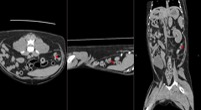

狗狗後腳癱瘓也有可能是血栓 不一定是骨骼神經肌肉問題喔

後肢癱瘓的柴柴經由他院轉診來築心做電腦斷層掃瞄因為狗狗以前病史有椎間盤突出問題

所以以為是脊椎問題想要來評估手術

掃瞄結果診斷為動脈血栓造成

主動脈血栓栓塞是一種急性且危及生命的疾病,當血液凝塊從心臟或其他部位脫落,經過血液循環流向並卡住動脈中的某些血管,造成局部的血液供應中斷、相應部位的器官或組織缺氧,將引起疼痛、損傷甚至壞死。

此患犬在電腦斷層影像以及後續追蹤的超音波下都可見明顯血栓影像